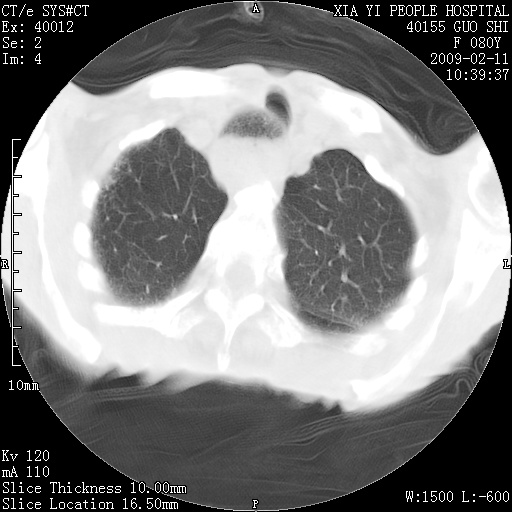

以下是引用随光逐影在2009-2-16 16:34:00的发言:[br]1)考虑右前纵隔皮样囊肿。2)双侧少量胸腔积液。

以下是引用zjzjr在2009-2-16 17:30:00的发言:[br]支持囊性畸胎瘤 双侧少量胸腔积液。